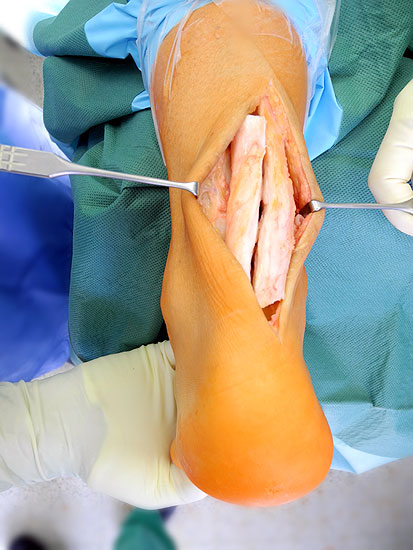

Technik

• schräge, zur Achse des Calcaneus rechtwinklig verlaufende Inzision 4 bis 5 cm mit Beginn ca. 2 cm posterior der Fibulaspitze in Richtung plantares Calcaneo-Cuboidal-Gelenk (oder in der Mitte zwischen Fibulaspitze und Ende der weichteiligen Ferse).

• Präparation durch das Subcutangewebe posterior der Peronealsehnen, auf den N. suralis muss geachtet werden.

• Darstellen der lateralen Calcaneus-Wand auf einem 1 cm breiten und parallel zum Hautschnitt verlaufenden Streifen.

• Umfahren des Calcaneus mit Hohmann Hebeln und Markieren der Osteotomie mit 2 1.6 Kirschnerdrähten; Kontrolle der korrekten Osteotomie-Ebene im BV, diese sollten, da in der Regel keine Verkürzung oder Verlängerung des Rückfuβes gewünscht ist, in der axialen Projektion genau rechtwinklig zur Achse des Calcaneus verlaufen; seitlich beginnt die Osteotomie proximal etwa 2 cm anterior des Achilles-Ansatzes und läuft etwas schräg nach distal-anterior.

• Sägen der Osteotomie mit vorsichtigem Eröffnen der medialen Kortikalis, um die dortigen neurovaskulären Strukturen zu schützen (evtl. palpierenden Finger gegenhalten) (Abb. 2).

• Mobilisation der Weichteile und Aufspreizen der Osteotomie mit Knochenspreizer, gelegentlich muss das Skalpell vorsichtig zum Durchtrennen fibröser Gewebsanteile medial und plantar eingesetzt.

• Je nach gewünschten Ausmass der Korrektur Lateralisation des Tuberfragmentes um 6-10 mm; zur besseren Verschiebung des Fragmentes hat sich der Einsatz des Rasparatorium bewährt, durch die Dorsalflexion des Fuβes, kann die Korrektur-Position vorläufig fixiert und Kompression auf die Osteotomie erzielt werden; daneben kann die vorläufige Fixation auch mit Kirschnerdrähten über eine dorsoplantare Querinzision 3 cm erfolgen.

• Häufig verschiebt sich das Tuber-Fragments bei der Korrektur etwas nach proximal, was aber bei steilem Calcaneus (hoher “calcaneal-pitch” Winkel) erwünscht sein kann.

• Definitive Fixation über die dorsoplantare Querinzision mittels Schrauben (normale 3.5 mm Kortikalsischrauben sind hier völlig ausreichend).